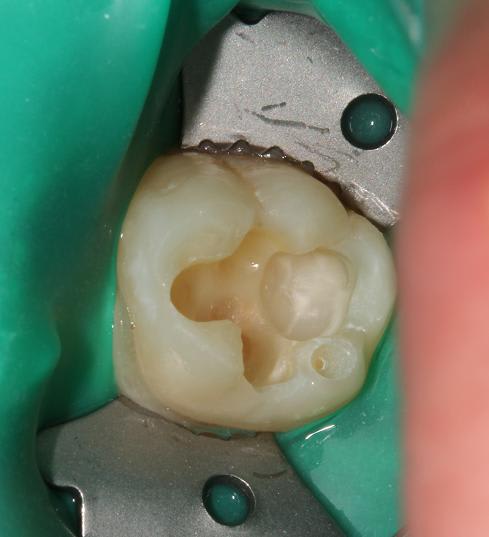

Quelques photos pour illustrer le sujet initial. Dommage que ces dents n'aient jamais eu de sealants.

Pour l'effraction pulpaire sur dent asymptomatique, je fais le protocole que Choixpeau avait mis sur le forum : hypochlorite puis adhésif directement au contact. Aucun problème à court terme pour le moment.

Si effraction plus importante : MTA.